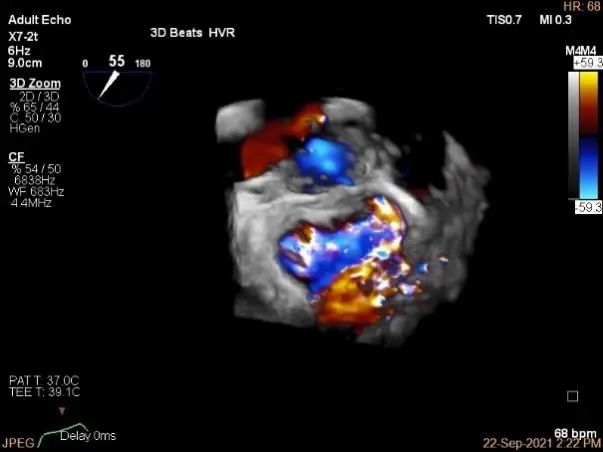

术中超声

P2区脱垂,宽14.8mm,Gap:3.3mm

3D-color,返流重度,3+级

三维评估两个夹子位置

3D-color再次确定未见残余分流